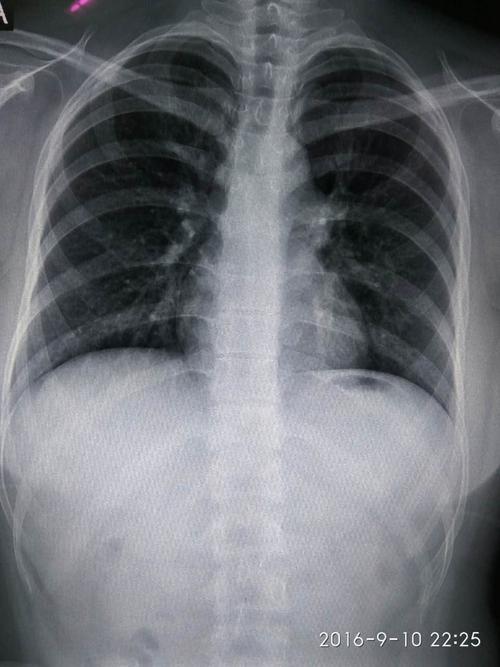

求高手看一胸片

有学医的同学看下x胸片嘛!

不正常的胸片图

正常胸片和异常胸片